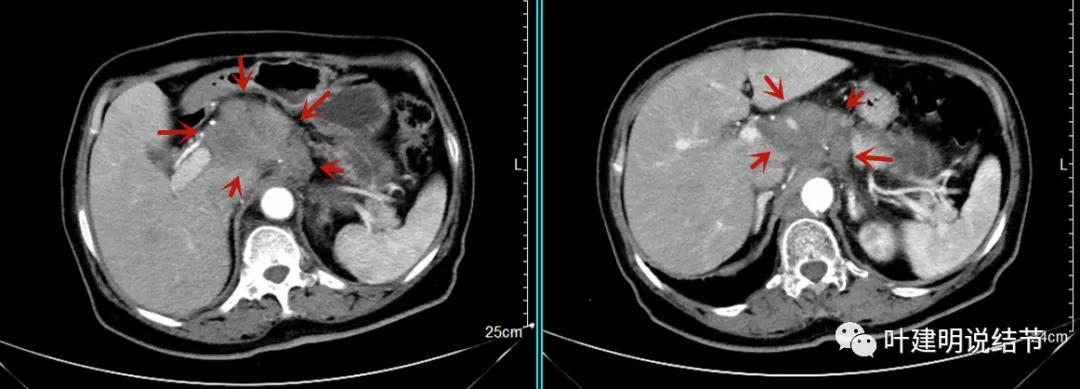

我们选择了“特瑞普利单抗加多西他赛加卡铂”的化疗加免疫治疗方案。我们来看经过一个周期治疗后肿瘤改善情况的对比:

上图左侧是治疗前的,右侧图像是差不多同一层面(因原肿瘤挤压,很难完全找出同一平面),可见病灶明显缩小改善了!下面是复查时的CT影像报告: